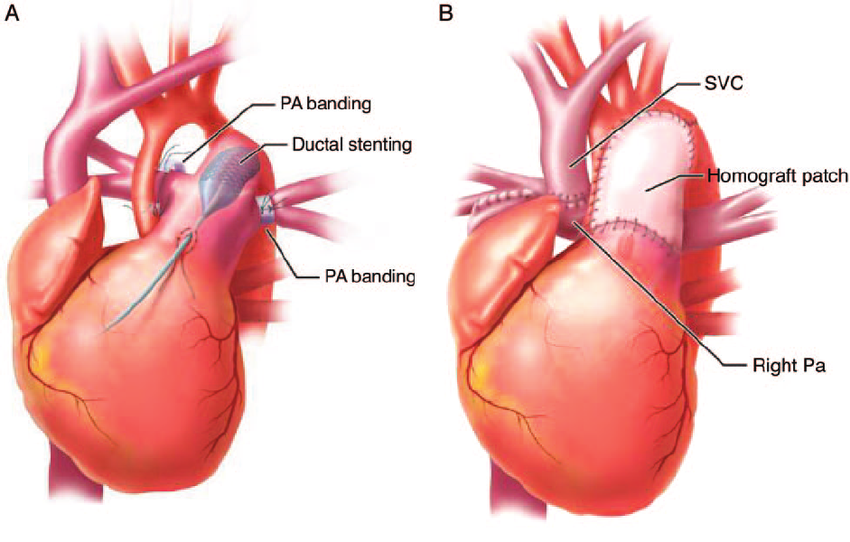

Overview

Package includes:

Days in hospital : 6 to 7 Days (For patient and one attendant)

Days in hotel : 12 Days (For patient and one attendant)

Room type in hospital : Shared

Room type in hotel : Private

Hotel category: Standard

Value added benefits of the PA Banding: